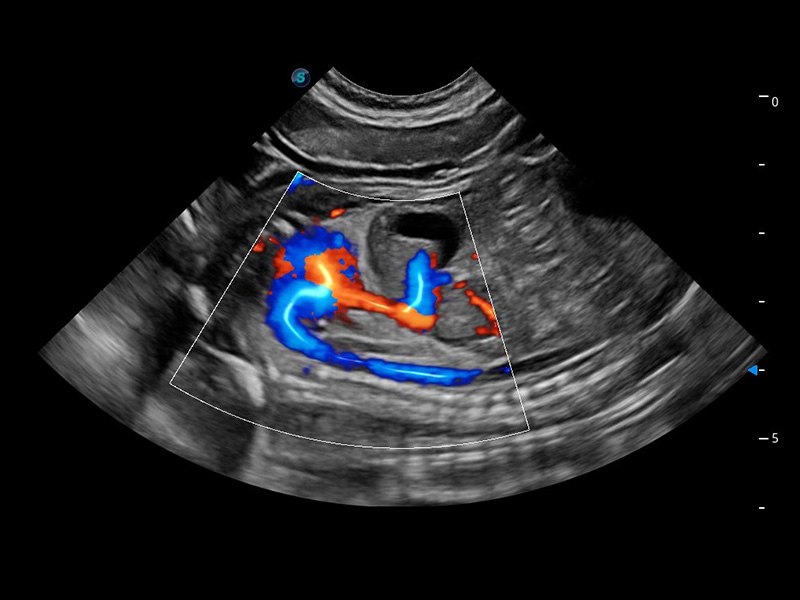

ProPet 60 作为一款高端台式动物超声设备,为动物医生的日常诊断提供了一系列贴合动物临床需求、解决临床实际问题的高级成像功能。凭借全系列高清探头,满足医生对腹部、心脏、生殖、浅表、肌骨等成像的所有需求,切实帮助您提升检查效率,提高诊断信心。

动物是人类最亲密的朋友和最值得信赖的伙伴。1xBET也一直致力于探索动物专用的超声影像解决方案。 全新推出的ProPet系列,是1xBET在动物超声影像智能化、专业化、精准化的一次跨越式革新。动物不能用言语来表述自己的不适,通过超声影像,ProPet系列搭建了动物医生与不同物种沟通的“桥梁”,为动物医生注入了“治愈之力”。